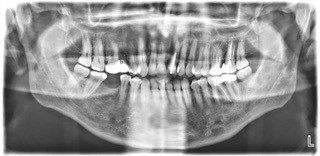

Wykonano na podstawie przygotowanych wcześniej przez technika Jacka Skrzyńskiego z PreciLab wax-upów – preparacje zębów, wyciski masą polieterową Impregum. Dodatkowo, zęby zostały zabezpieczone koronami tymczasowymi.

Następnie, pracownia Preci Lab wykonała pracę z wykorzystaniem łączników indywidualnych Atlantis oraz korony na tlenku cyrkonu i onlaya’e E-max. Pacjent zyskał komfort gryzienia i piękny uśmiech, dzięki wykonaniu pracy w centralnej relacji oraz pozbyciu się bakterii z kanałów korzeniowych (poprzez leczenie kanałowe).